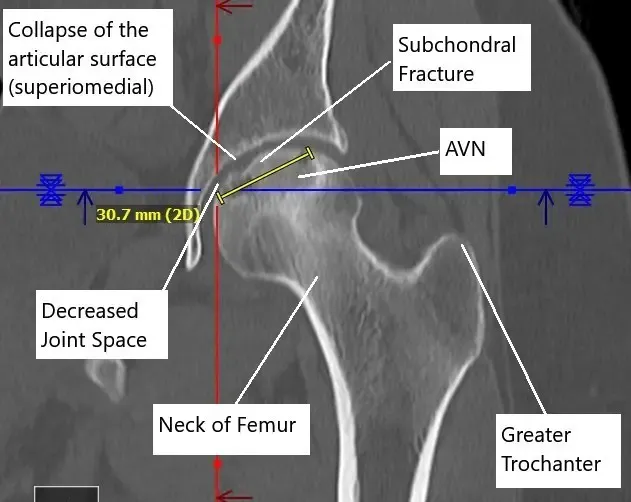

A CT without contrast revealed progression of the avascular necrosis since the core decompression surgery. Avascular necrosis involved the majority of the femoral head, most pronounced superomedially and measuring 3.1 x 3.8 cm.

There was a subchondral fracture superomedially and a mild collapse of the articular surface. There was a mild narrowing of femoral acetabular joint space superomedially with a suggestion of a small joint effusion.